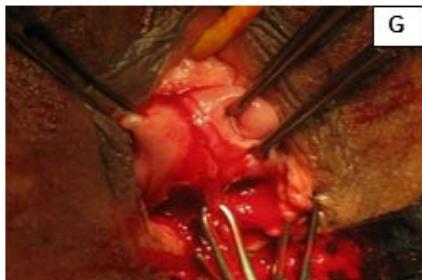

#### Case 5: Uterine didelphys with high vaginal septum

A 29-year-old, female married for 2 years, nulligravida, presented with dyspareunia and primary infertility. Patient was a known case of uterine didelphys with vertical vaginal septum and gives history of being operated for imperforated anus in childhood. Pelvic examination showed complete vertical vaginal septum with two vaginal canal leading to two separate cervices. Both the cervices were short and flushed with vagina and UCL was measured as 3 inches on both sides. USG showed uterine didelphys with vertical vaginal septum. Patient underwent vaginoplasty and metroplasty and post operatively, dilatation with Hegars No. 28 dilators was advised. The patient was able to have normal sexual function. (Fig. 5)

Figure 5: A: Uterine didelphys. B: Opening cavity during metroplasty. C: Complete vertical septum infiltrated with saline. D: Vaginal canals opening into two separate cervical openings. E: Anterior lip of cervices held with Allis' forceps and vertical incision taken over septum. F: Plane of dissection maintained along the septum. G: Redundant mucosa cut. H: Cut ends sutured with vagina with Vicryl 3-0. I: Vagina with two cervices.